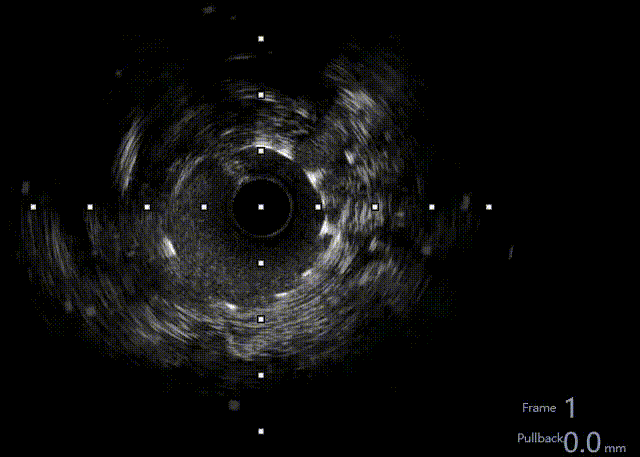

建立轨道后,交换为Runthrough 导丝后,行IVUS检查证实导丝位于血管真腔。

利用IVUS精确选择支架落脚点。

IVUS显示支架贴壁良好,未见夹层,RCA中远段MSA 7.41mm²,术毕。